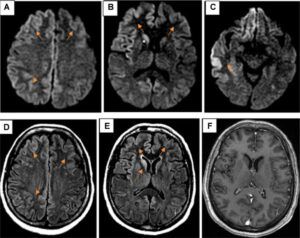

Un studiu suedez despre utilizarea telefoanelor mobile a scos la iveală o legătură între expunerea la radiaţii electromagnetice şi riscul tumorilor la creier.

Telefoanele mobile emit o formă de radiaţii electomagnetice neionizate care pot fi absorbite de celulele şi ţesutul din zona cu care vin în contact, precum capul şi gâtul.

Acest nou studiu sugerează că persoanele care folosesc telefoane mobile pentru mai mult de un îşi cresc cu 70% riscul de cancer la creier. Cei care folosesc telefoane mobile pentru mai mult de 25 de ani, riscul creşte cu 300%

La jumătatea anului trecut, Organizaţia Mondială a Sănătăţii a încadrat radiaţiile provenite de la telefoanele mobile în categoria „posibil cancerigene”. Cafeaua şi DTTul sunt în aceeaşi categorie. A fost pentru prima dată când această instituţie are o reacţie clară, dat fiind faptul că studiile realizate de-a lungul vremii au prezentat concluzii diametral opuse: unele au arătat că mobilul este inofensiv, altele că determină dezvoltarea de tumori maligne. Preşedintele grupului de cercetare care a impus decizia OMS, Jonathan Samet de la Universitatea din California de Sud, SUA, a declarat că datele existente sunt suficient de puternice pentru a încadra efectele vorbitului la mobil în categoria 2B, de risc crescut de cancer.